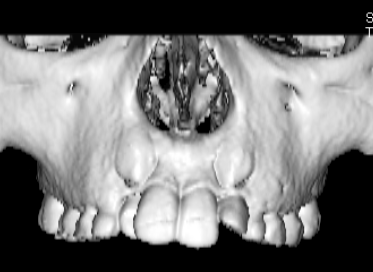

FX(フェイシャルアキシス)は85度なので東洋人の平均値に近く、下顎が前方に過剰成長するリスクは強くはありません。

しかしやはり上顎は劣成長で、下顎が優位な状態ではあります。

上下顎のギャップはありますが、顔面自体の幅径は良好な値を示していますので、スペース不足は拡大することによって解決できポテンシャルはあると考えられます。

左右の非対称もさほど強くありません。

骨年齢は実年齢よりも低めなので、今後下顎の旺盛な成長が見込まれます。

検査時のレントゲン分析では、上下顎の関係は、上顎の劣成長があり下顎前突傾向という値がでておりましたが、前歯ジャンプ後はフェイスマスクの効果もあり、上下顎の関係は正常化しています。

上顎が若干優位になっていますので、今後の下顎の成長のための貯金になっているくらいです。